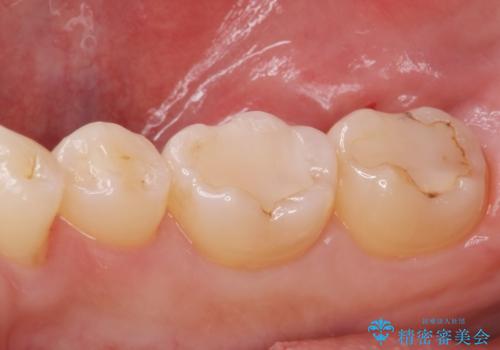

古い樹脂の劣化 セラミックインレー治療

適合の良い詰め物が入りました。

もう一つの治療も現在検討中です。